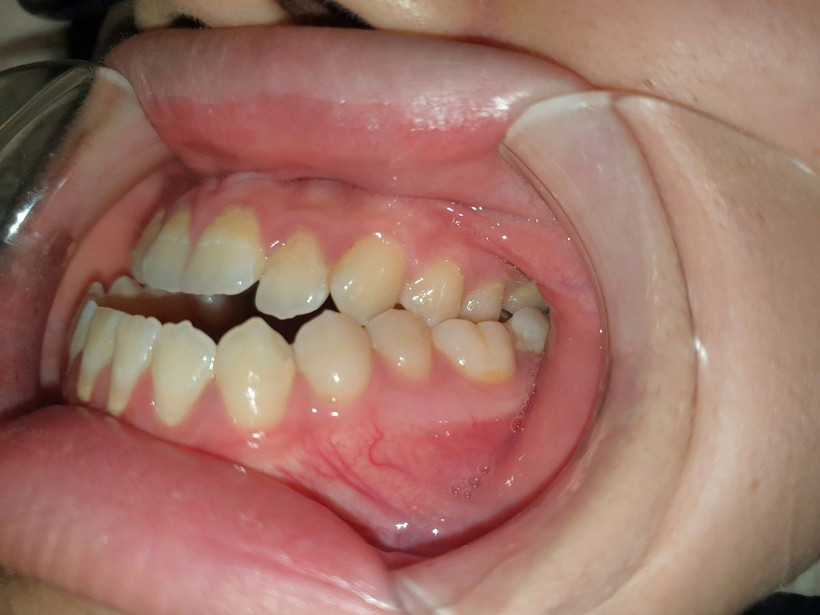

Khớp cắn ngược (răng trên ở sau răng dưới).

Dấu hiệu của khớp cắn ngược là răng cửa trên ở sau so với răng hàm dưới (bình thường răng cửa trên ở trước răng cửa dưới từ 2 đến 4 mm); phần mặt giữa phẳng, thiếu độ lồi, vùng rãnh cười có thể lõm; vùng cằm nhô ra trước và có thể lệch sang một bên, bệnh nhân có thể có kiểu hình mặt “lưỡi cày” hoặc hình “trăng khuyết” tương tự như mô tả gương mặt phù thuỷ trong văn học phương tây.

Khiếm khuyết về ngoại hình này rất khó sửa chữa bằng các liệu pháp nguỵ trang như nắn chỉnh răng, tiêm chất làm đầy hay botox và có ảnh hưởng tiêu cực đến cơ hội trong cuộc sống cũng như sự tự tin của bệnh nhân. Răng cửa dưới sẽ có xu hướng ở trước răng cửa trên.

Trong trường hợp nặng sẽ răng cửa hai hàm không chạm được vào nhau khiến cho bệnh nhân ăn uống khó khăn, không cắn đứt được thức ăn bằng răng cửa. Việc phát âm cũng có thể bị ảnh hưởng nặng nề do răng và môi cũng là một phần của bộ máy phát âm. Khi bộ răng và môi không hài hoà (không chạm được vào nhau), sẽ có một số âm phát ra khó khăn như âm /f/ hoặc /v/ dẫn đến việc bệnh nhân có thể bị ngọng.

Các răng hai hàm chen chúc, khấp khểnh, răng cửa dưới dựng thẳng hoặc ngả về phía sau tạo thành các khe kẽ nhỏ khó vệ sinh, xương ổ răng (phần xương bao bọc chân răng) mỏng làm cho răng dễ bị rụng khi về già.